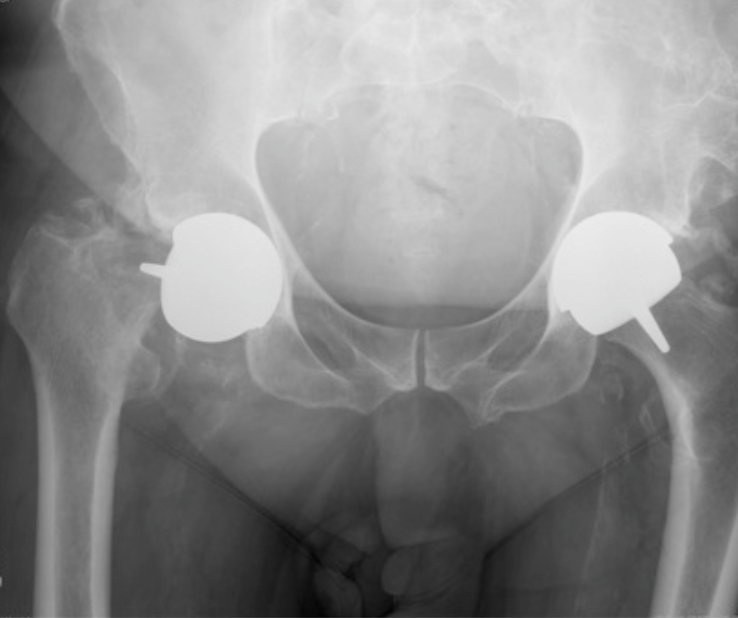

Birmingham hip resurfacing

| Head size mm | 20 year revision % |

|---|---|

| < 45 | 31 |

| 45-49 | 15 |

| 50-54 | 8 |

| > 55 | 6 |

| Male | Female | |

|---|---|---|

| 5 year | 2.3 | 6.4 |

| 10 year | 4.1 | 14 |

| 15 year | 6.2 | 18.7 |

| 20 year | 8.1 | 22.1 |

Indications

Male / OA / good bone stock / large femoral head size